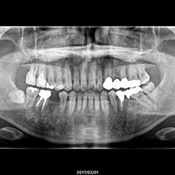

検査・診断

カウンセリング後は、お口の状態を調べるため、レントゲン撮影や歯周病検査などを行います。